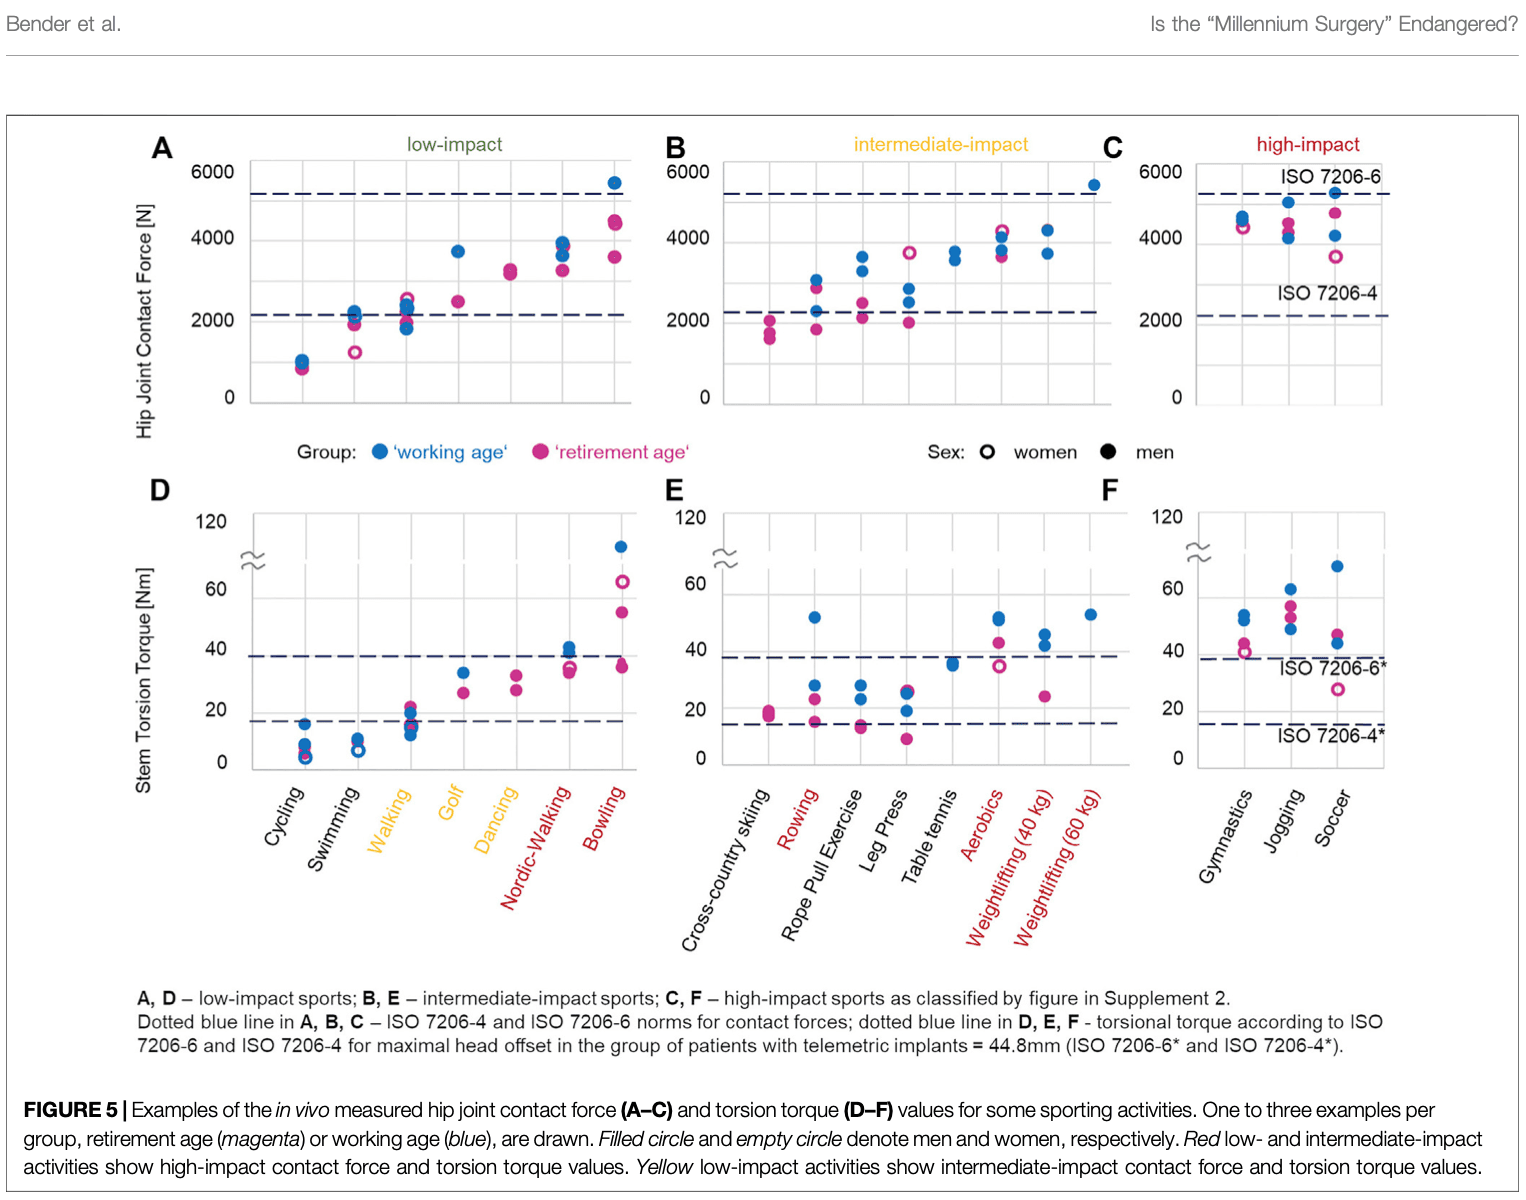

Има какво да се каже за тази обобщаваща таблица. Bender, 2022 г. измерва in vivo сили на контакт със ставите и усукващи моменти и установява, че боулингът, който се счита за дейност с ниско въздействие, например, предизвиква по-високи сили на контакт със ставите и усукващи моменти в сравнение с футбола с високо въздействие. Освен това те установяват, че телесното тегло и индексът на телесна маса оказват влияние върху тези сили по време на ежедневни дейности.